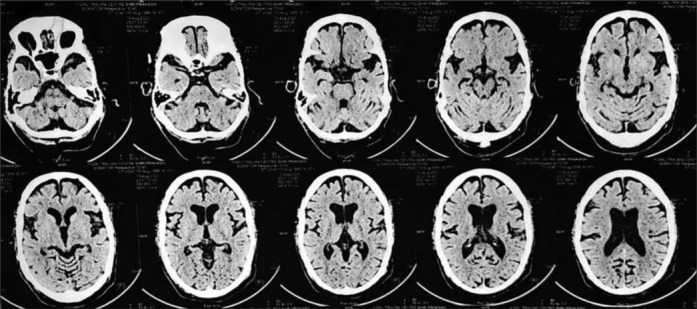

紧张症是一种以行动不便和交流障碍为特征的复杂综合征,在不同认知障碍和潜在痴呆的个体中,对劳拉西泮治疗的反应不同。本研究检查了一个病例系列,涉及四个不同的紧张性精神病患者,以阐明影响劳拉西泮反应的因素。虽然劳拉西泮作为一种gaba能调节剂,在某些情况下可以有效缓解症状,但其在其他情况下的有限影响突出了各种痴呆的潜在病理生理和治疗机制之间复杂的相互作用。本摘要提供了对神经化学通路、紧张症症状和治疗方法之间复杂关系的见解,揭示了在认知障碍和痴呆的背景下管理紧张症的复杂性。

Catatonia, a complex syndrome characterized by immobility and communication impairment, presents with varying responses to lorazepam treatment among individuals with different cognitive impairments and underlying dementias. This study examines a case series involving four distinct catatonic patients to elucidate the factors contributing to the variable lorazepam response. Although lorazepam, a GABAergic modulator, can effectively alleviate symptoms in some cases, its limited impact in others highlights the intricate interplay between the underlying pathophysiology of diverse dementias and treatment mechanisms. This abstract provides insights into the intricate relationship between neurochemical pathways, catatonic symptoms, and treatment approaches, shedding light on the complexities of managing catatonia in the context of cognitive impairments and dementias.